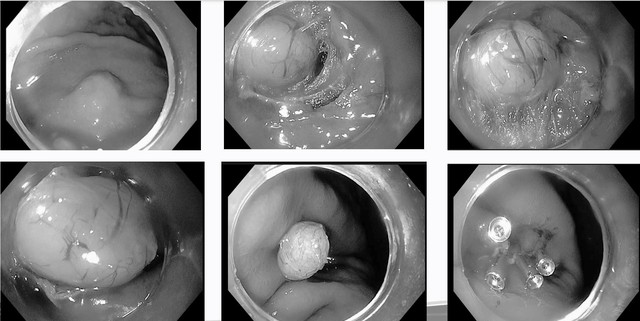

Hình ảnh sau can thiệp bằng kỹ thuật STER (Submucosal Tunneling Endoscopic Resection). Ảnh: BVCC.

Các bác sĩ tiến hành rạch một đường niêm mạc ở vùng cách xa tổn thương (thông thường cách khối u khoảng 1–5 cm), sau đó đưa ống nội soi vào lớp dưới niêm mạc và di chuyển dần về vị trí khối u, tạo thành "đường hầm" để tiếp cận. Sử dụng kỹ thuật phẫu tích cắt dưới niêm mạc (ESD) để cắt bỏ toàn bộ khối u một cách chính xác. Sau khi đã cắt bỏ hoàn toàn khối u, bác sĩ tiến hành đóng đường rạch niêm mạc bằng clip.

Cắt u dưới biểu mô dạ dày bằng kỹ thuật STER (Submucosal Tunneling Endoscopic Resection) – một phương pháp nội soi hiện đại, ít xâm lấn, giúp người bệnh hồi phục nhanh và hạn chế biến chứng. Ảnh: BVCC.